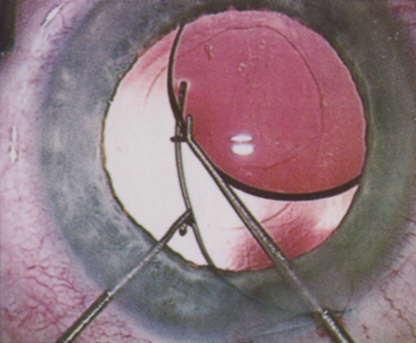

Many patients are most bothered by cataract-induced glare. For these patients, acuity testing under glare situations is indicated. There are several methods to assess visual acuity reduction by glare. The choice of method is often best dictated by the patient's history. If a patient complains of glare problems in the supermarket, or other uniformly illuminated environment, the brightness acuity test can be performed (Mentor Ophthalmics). For this test, the specially illuminated handpiece is held in front of the tested eye using best spectacle correction (Fig. 1). The Snellen acuity is rechecked and can be recorded on each of three light settings.